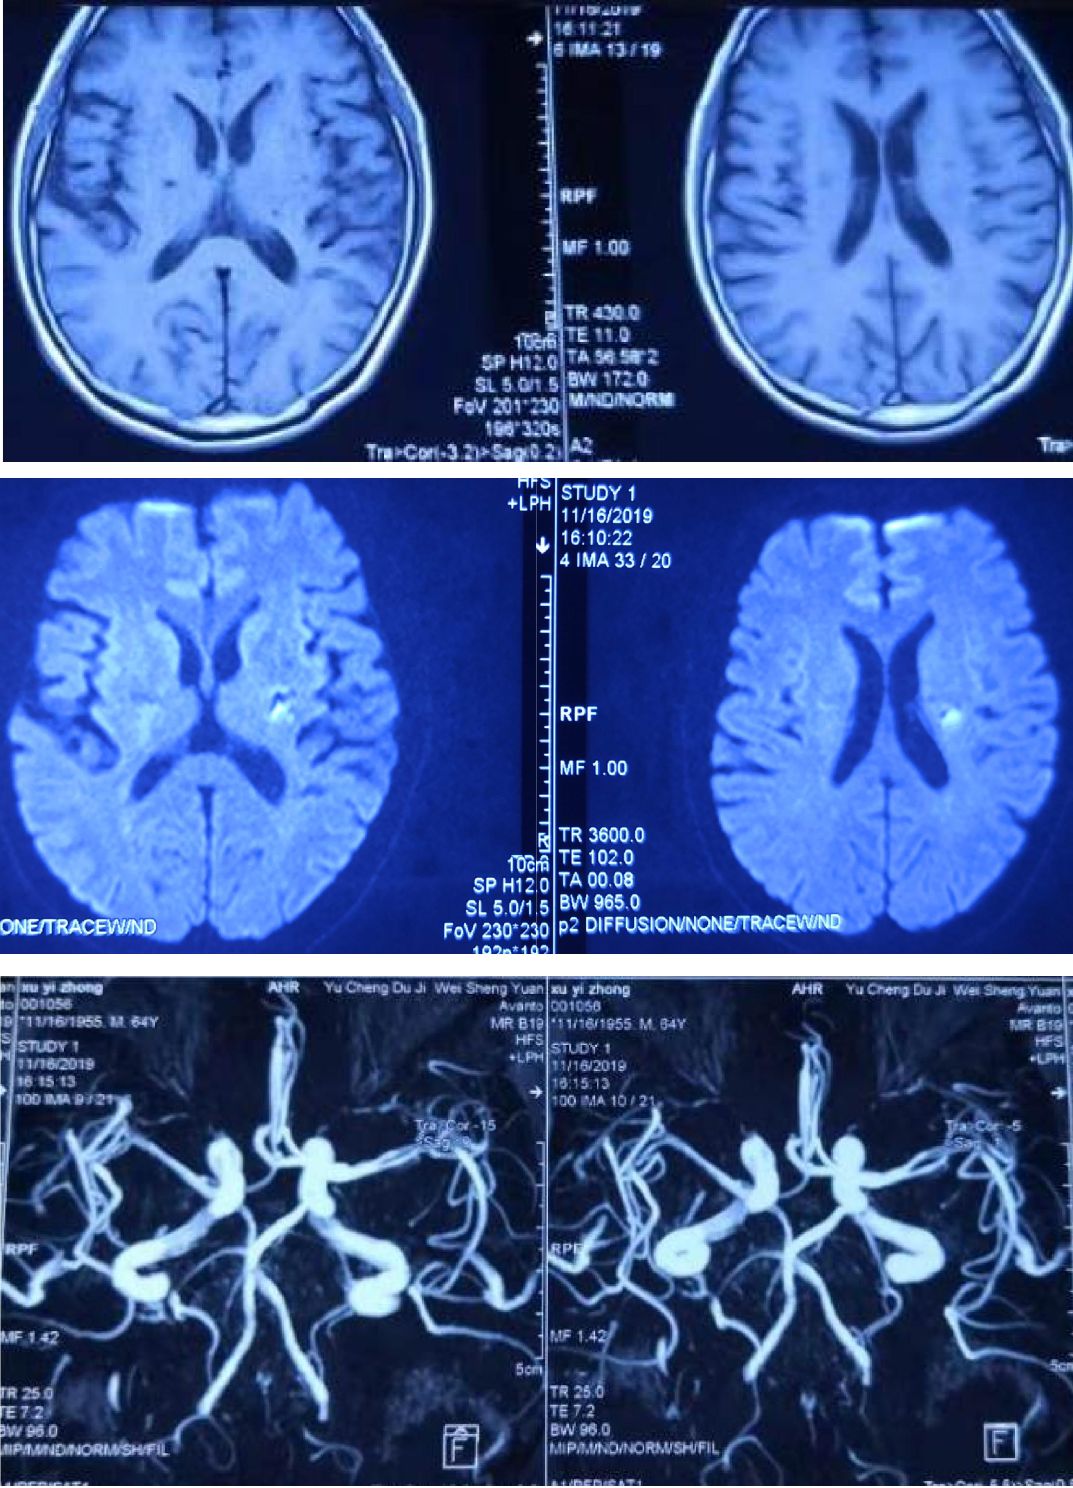

男性67岁,进展性头晕、行走欠稳。影像可见双侧桥臂、脑桥相对对称弥散受限;MRA可见椎基底动脉未见显影。

诊断: 后循环分水岭梗死。

1. 后循环分水岭梗死主要发生在小脑交界区,多位于小脑上和小脑后下动脉之间。

2. 脑干的分水岭梗死常位于脑桥被盖部和基底部连接处的内侧区。

前循环分水岭大家耳熟能详,后循环分水岭可能听起来有点陌生,通过这个病例复习一下相关知识点,遇到类似病例可以推断病因及分型。